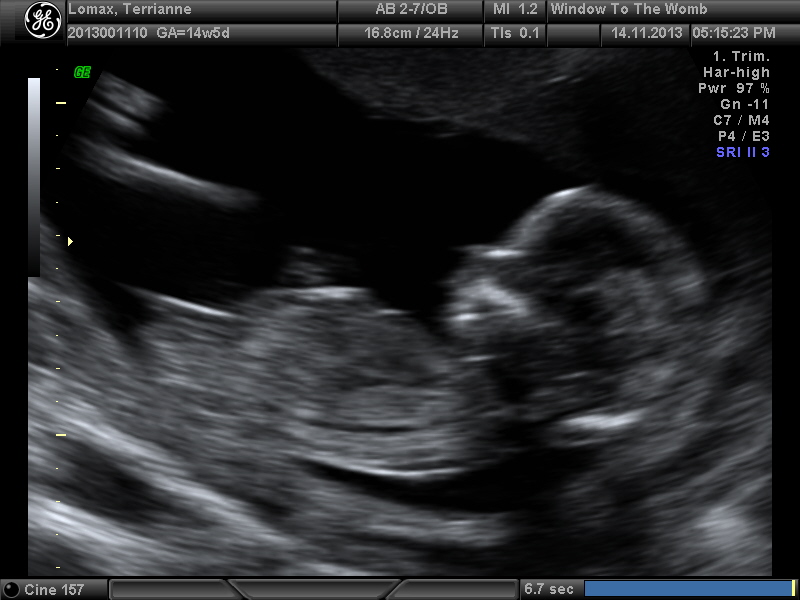

I posted a scan picture of my 13plus3 scan and most was boy guessers u had a scan today at 14plus5 she said she could see but couldn't tell me as I need to be at least 15weeks :( . So could you take a look and let me know if you see any clues.